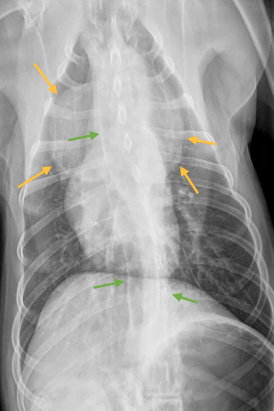

In verband met het regurgiteren werden de volgende röntgenfoto’s gemaakt:

Röntgenonderzoek #

Er is een goed omschreven afgeronde forse massa zichtbaar ter hoogte van het craniale mediastinum, waardoor de trachea naar dorsaal wordt verplaatst.

De oesofagus toont over de hele lengte van de thorax fors gedilateerd en met lucht gevuld. Overige thoracale structuren, zoals de pleurale holte, longen, hartschaduw en omgevende benige structuren tonen röntgenologisch onopvallend.

In het abdomen toont de maag fors gedilateerd en gevuld met lucht. De maag bevindt zich op een normale positie.

Conclusie #

Forse massa in het craniale mediastinum (ddx thymoom, thymussarcoom, mediastinale cyste of maligne lymfoom) en mega-oesofagus.

Wat laten deze röntgenfoto’s zien?

De röntgenfoto’s tonen de massa in het craniale mediastinum (oranje pijlen), de megaoesofagus (groene pijlen) en gedilateerde maag.